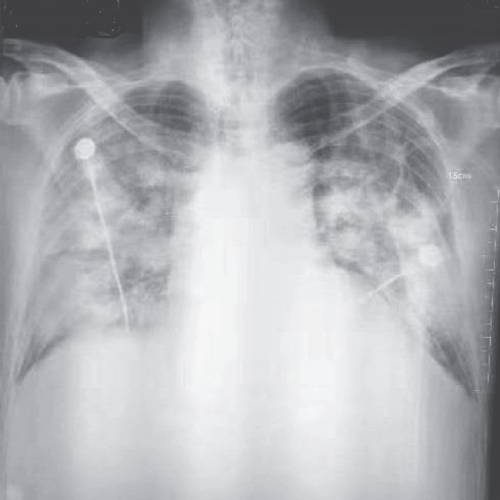

Para mais detalhes e informações atualizadas sobre a nova epidemia de coronavirus, acesse os dois recentes artigos publicado no New England Journal of Medicine clicando aqui (1), ou clicando aqui (2), ou pela nossa Central de Downloads. A foto que ilustra essa matéria foi retirada da referência 1.